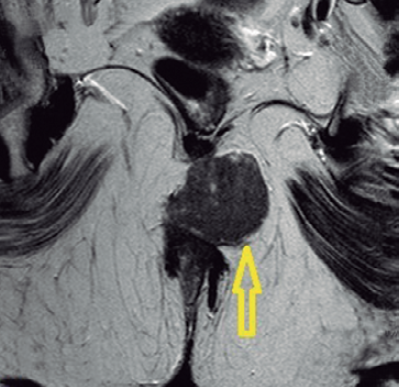

Carlos Bustamante Recuenco, Sagrario Fuerte Ruiz, Raquel León Ledesma, Eva María Lumbreras García

|